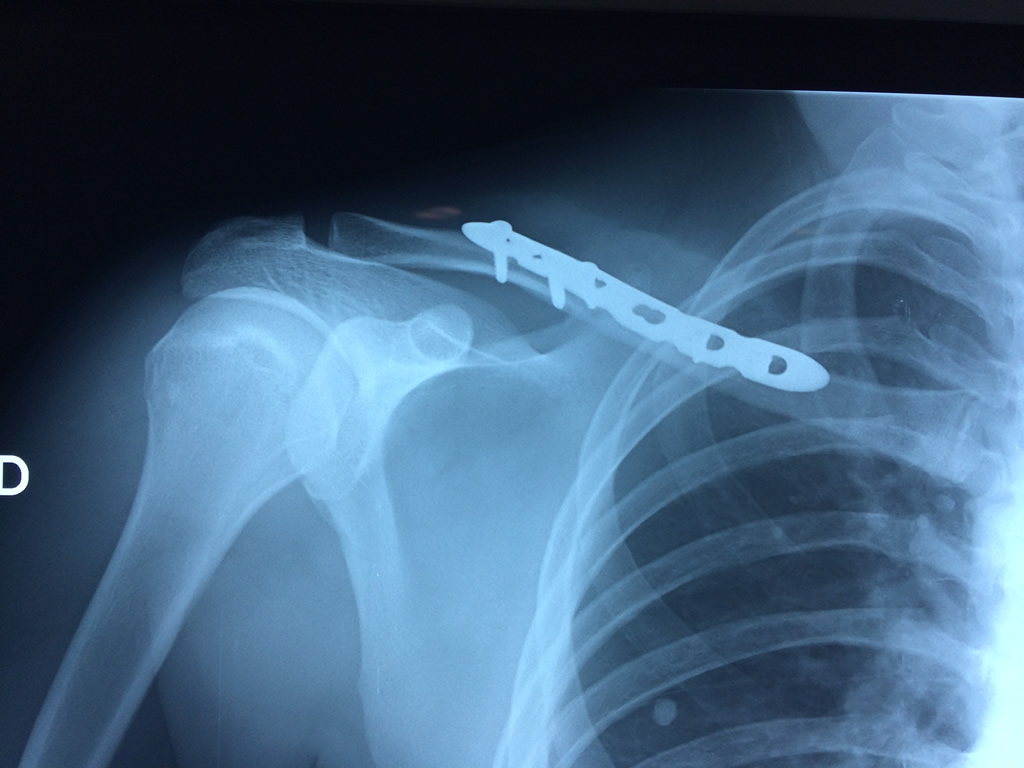

Fémur - Clavícula

La clavícula es un hueso largo, con forma de "S" itálica, situado en la parte anterosuperior del tórax. Junto con la escápula forman la cintura escapular. Se puede palpar por toda su longitud y se extiende del esternón al acromion de la escápula, siguiendo una dirección oblicua lateral y posterior.

Se considera el único medio de unión entre el miembro superior y el tórax. A pesar de su aspecto, similar al de un hueso largo, posee una estructura semejante a la de un hueso plano, ya que carece de epífisis y de diáfisis, lo que la harían entrar dentro de la clasificación de hueso largo. Carece de un canal medular propiamente dicho.